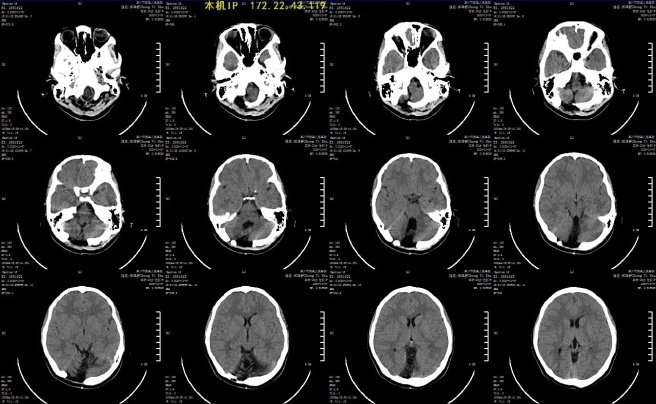

歷史的時(shí)針拔回到1999年,小鄭出生26天,出現(xiàn)嘔吐不止,焦急的父母將她送到惠州市人民醫(yī)院(現(xiàn)惠州市第三人民醫(yī)院)急診,頭顱CT檢查發(fā)現(xiàn):小腦大量出血。病情進(jìn)展迅速,很快發(fā)展至雙瞳散大。醫(yī)生診斷:小腦出血并腦疝形成,考慮維生素K缺乏癥,需緊急手術(shù)救命。但是,當(dāng)時(shí)患者親屬和周圍很多人都持悲觀態(tài)度,認(rèn)為搶救成功率很低,即使活下來(lái),也可能殘留明顯后遺癥,很多人建議他們放棄治療。

當(dāng)年術(shù)前CT:小腦大量出血

手術(shù)取后顱窩正中切口,枕骨右側(cè)鉆孔打開(kāi)小骨窗,剪開(kāi)硬腦膜,血腫液涌出,反復(fù)沖洗清除血腫液,腦搏動(dòng)恢復(fù)良好。復(fù)查CT血腫清除干凈。

術(shù)后CT:骨窗開(kāi)顱,血腫清除干凈

隨訪22年,術(shù)后康復(fù)順利,生長(zhǎng)發(fā)育良好,智力正常,四肢無(wú)癱瘓。小鄭自學(xué)鋼琴已過(guò)五級(jí),現(xiàn)在是一名幼兒教師。